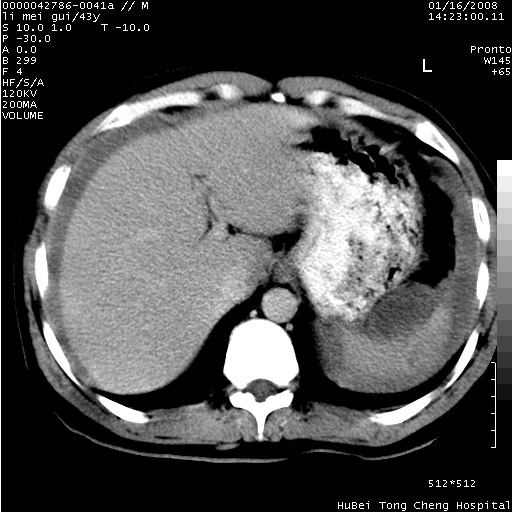

| 患者,男,43岁。突发腹痛2小时,面色苍白,难以平卧。自述近期无明确外伤史,为摩托车驾驶员。 腹部b超检查:脾脏中上极回声异常,肿瘤待排。 临床诊断:腹痛原因待查。 上中腹部ct轴位平扫+增强扫描(层厚10mm,螺距1.0,重建间隔10mm),图像如下: ![]() ![]() ![]() ![]() ![]() ![]() ![]() ![]() ![]() ![]() ![]() ![]() ![]() ![]() ![]() ![]() ![]() ![]() ![]() ![]() ![]() ![]() ![]() ![]() ![]() ![]() ![]() ![]() ![]() ![]() ![]() ![]() ![]() ![]() ![]() zrs发言:支持脾破裂 wwp发言:支持脾破裂并腹水。 xulianj发言:脾脏肿瘤破裂可能性大 zsl6918发言:不像肿瘤出血,考虑还是与外伤后引起的慢性出血有关 zzyy发言:平扫见肝周及脾周积液,脾内密度不均。脾内肿瘤较少见。还是外伤性脾破裂。 沈丘东方医院发言:脾门区一个不均匀强化病灶与其周液体相连多考虑脾占位破裂出血 yixianman001011发言:脾破裂并腹水是可以肯定的,具体原因多以肿瘤性破裂出血,脾脏淋巴瘤可能性大. 结果: 术后,经详细询问患者,其仔细回忆:一月前骑摩托时左侧腰部与别人有“轻微”触碰,因责任在自已,当时又无明显不适,未引起注意。 临床术后诊断:脾破裂并失血性休克(1.外伤性迟发性脾破裂。2.脾脏肿瘤破裂?) 术后标本病检:脾破裂并出血,未见明显肿瘤成份。 原贴地址:http://www.radinet.com.cn/forum_view.asp?forum_id=4&view_id=34070 |